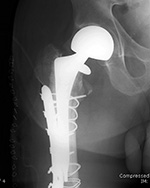

Revision total hip prosthesis |

Triflange acetabular component total hip revision arthroplasty with long femoral stem |

Triflange acetabular component total hip revision arthroplasty |

The revision prosthesis was placed because of an earlier periprosthetic fracture. There are two cable wires proximally and two cerclage wires distally. |

83 year-old woman |